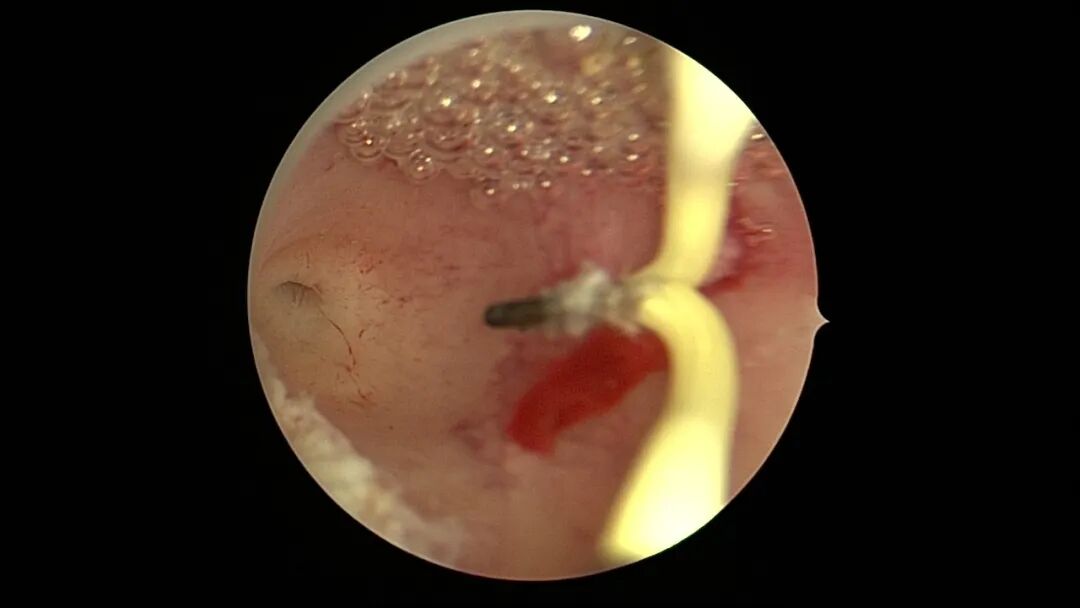

第三次宫腔镜:2021年9月,停经1+月,排除带环受孕,门诊B超提示宫腔粘连,节育环嵌顿。宫腔镜探查见γ型环嵌顿,宫腔广泛粘连,异物钳取环,环变形。单极电针分粘,恢复宫腔形态,显露双侧输卵管开口,右侧输卵管开口周围及宫底部分内膜正常,左侧宫角周围内膜薄,宫腔中部前后壁粘连创面集中,宫腔灌注生长激素。